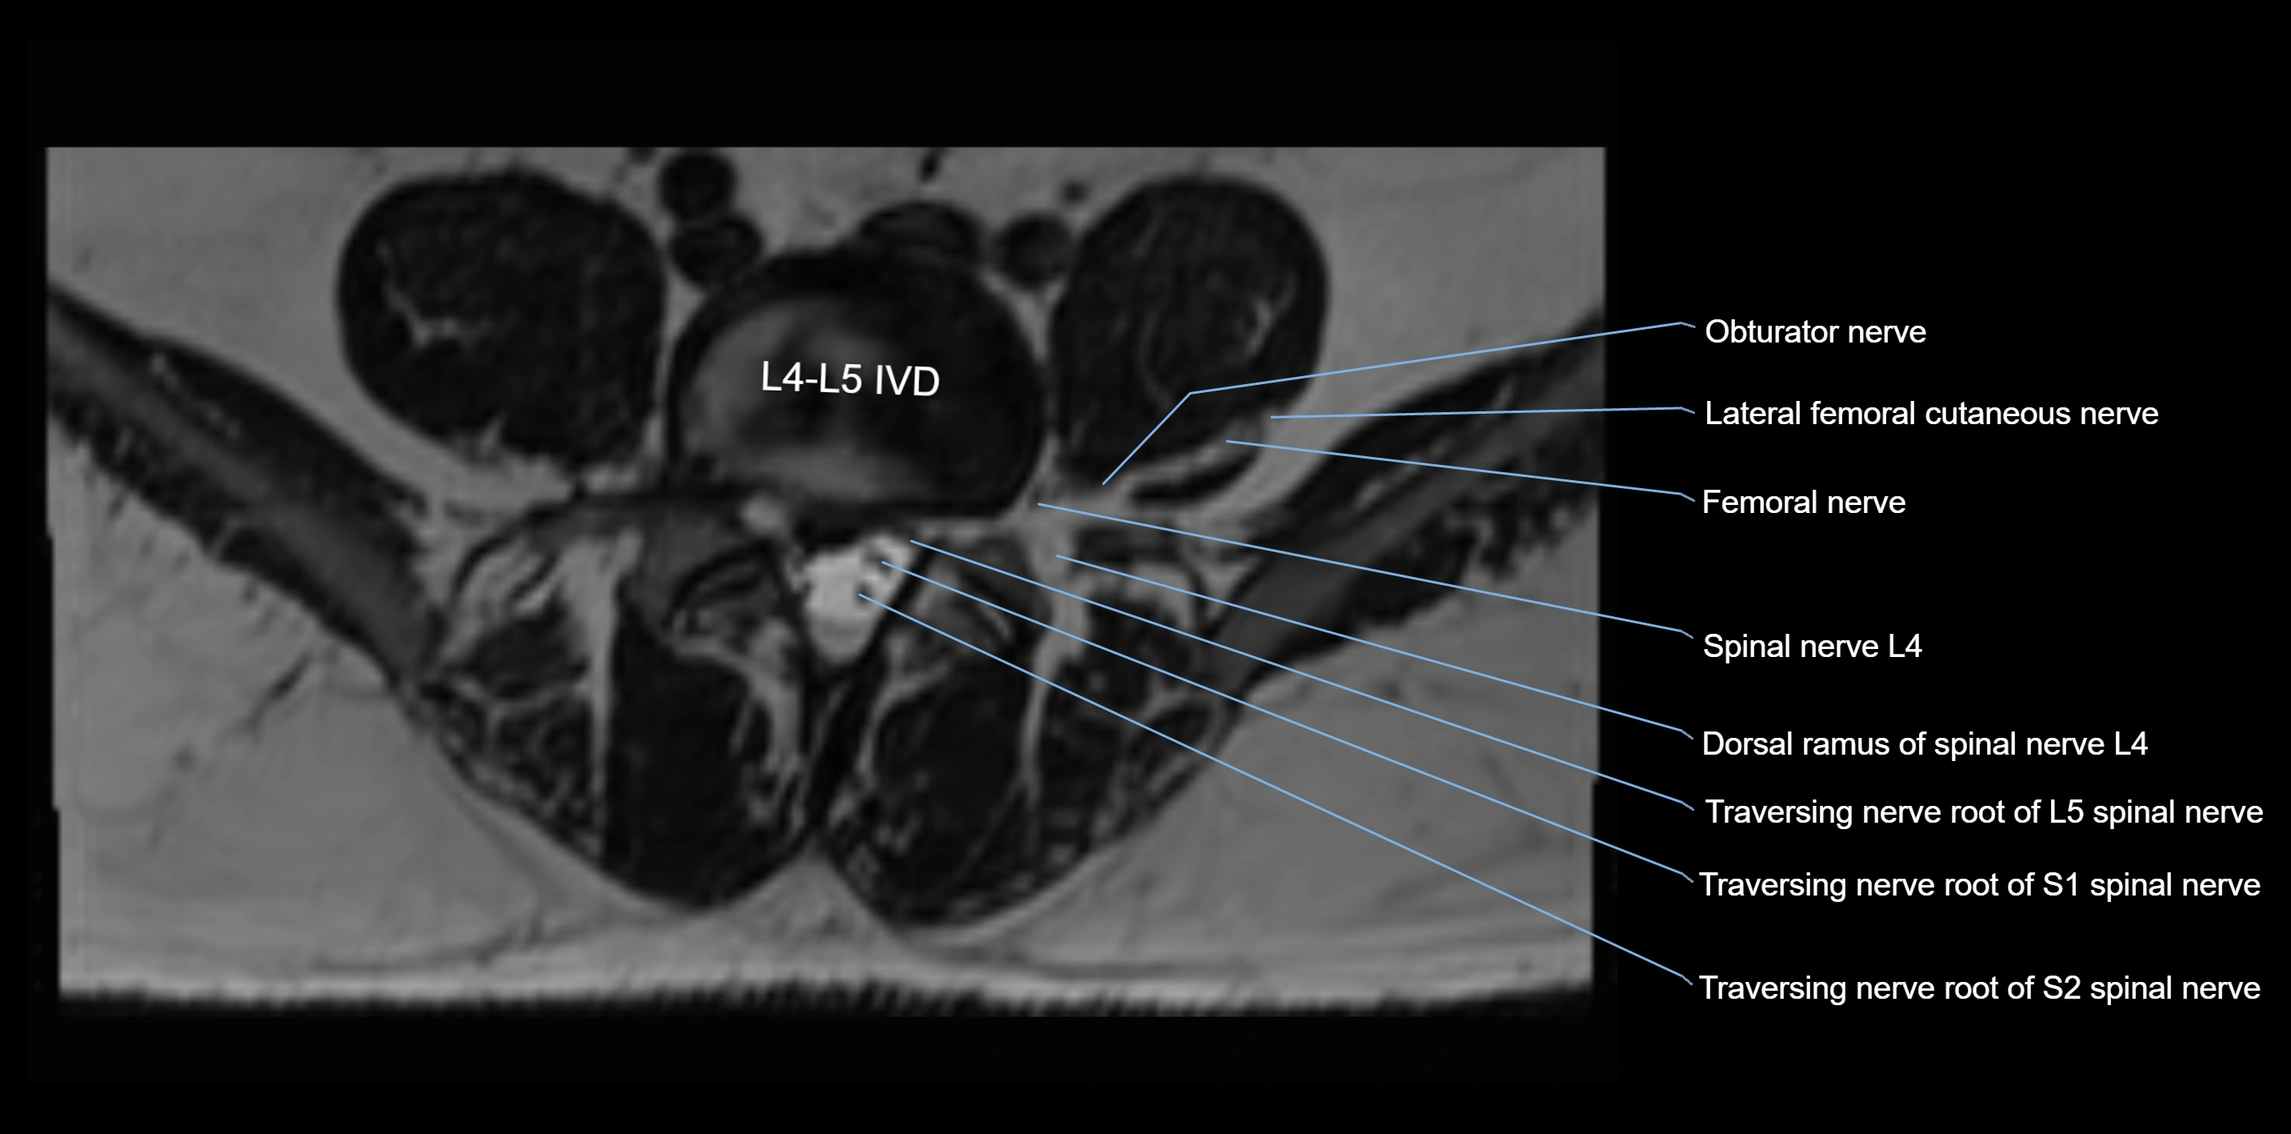

MRI image

image